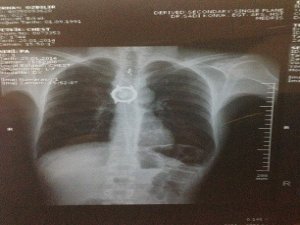

Bu tür vakaların ölümle sonuçlanabileceğinin altını çizen Dr. Duygu Mergan İliklerden, hasta yutma güçlüğü ve yemek yiyememe sorunuyla kliniklerine başvurduğunu söyledi. Yapılan tetkiklerde yemek borusunda yabancı cisimler olduğu tespit ettiklerini ifade eden Dr. İliklerden, “Hastanın filmlerini çektik ve içerisinde bazı cisimlerin olduğunu gördük. Hemen ameliyata alarak cisimleri çıkardık. Fakat saat parçası darlık nedeniyle yemek borusundan çıkmayınca hastayı açık cerrahiye aldık ve bu saati de çıkardık. Hastamız şu anda iyi sağlığına kavuştu" dedi.